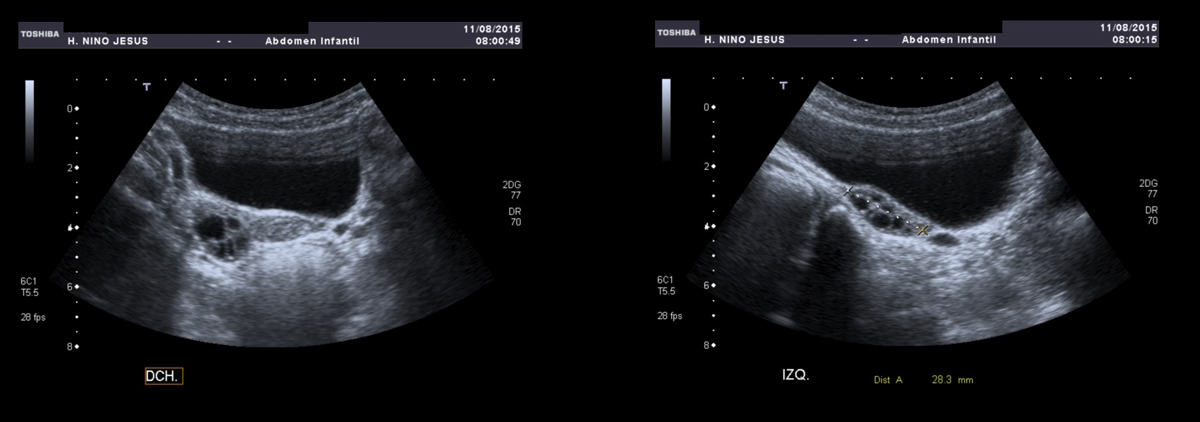

Ecografía pélvica:

• Útero de morfología prepuberal (medición aproximada 29 mm).

• Ovarios en el límite alto de la normalidad para la edad de la paciente (ovario derecho 21 mm e izquierdo 28 mm).

• Múltiples quistes foliculares en ambos ovarios.